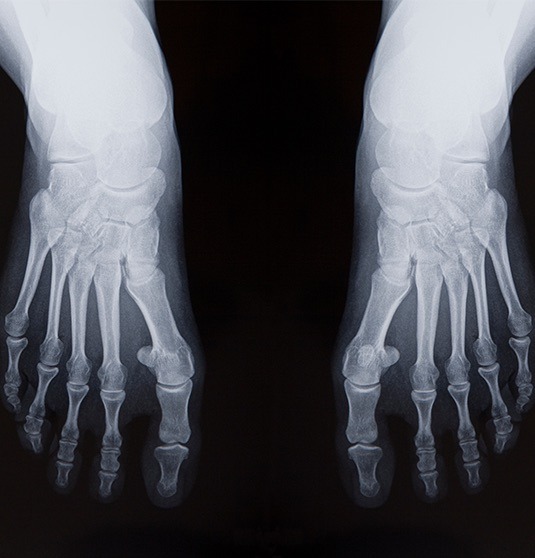

Splay Foot is challenging to live with, to say the least! The condition can affect one or both feet and often leads to various issues and symptoms that can interfere with daily activity and quality of life.

Let’s look at the causes, effects and treatments for Splay Foot: